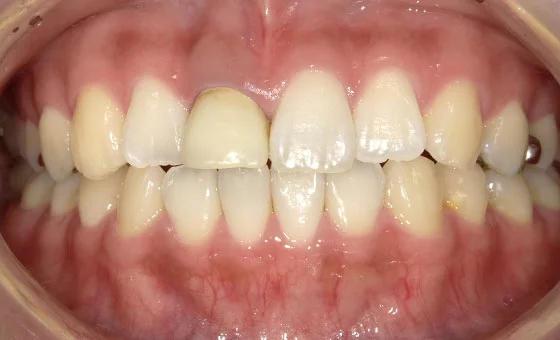

口腔内写真(5枚~)

さまざまな角度から「歯の状態」を撮影します。これにより、磨き残し、噛み合わせ、歯並び、見た目、虫歯などを丁寧にチェックしていきます。